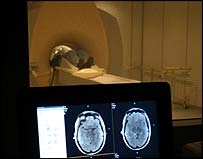

Exames de ressonância magnética

Exames de ressonância magnética foram utilizados na pesquisa

O estudo, realizado pela Universidade de Yale, nos Estados Unidos, mapeou a atividade cerebral de voluntários pedófilos e não-pedófilos por meio de exames de ressonância magnética, uma técnica que permite que a atividade cerebral seja gravada à medida que o paciente vai pensando.